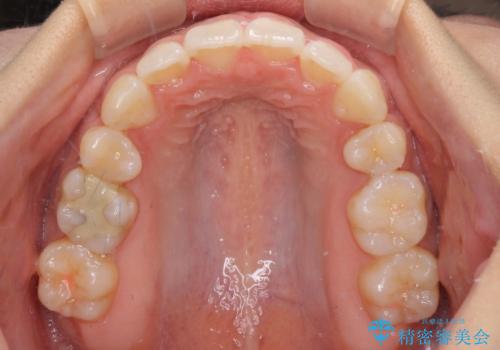

下顎の正中を上顎に合わせる処置が難航し、期間が長引きました。

最終的には上下の正中も合い、横顔の印象が変わるほどスッキリとした口元となりました。